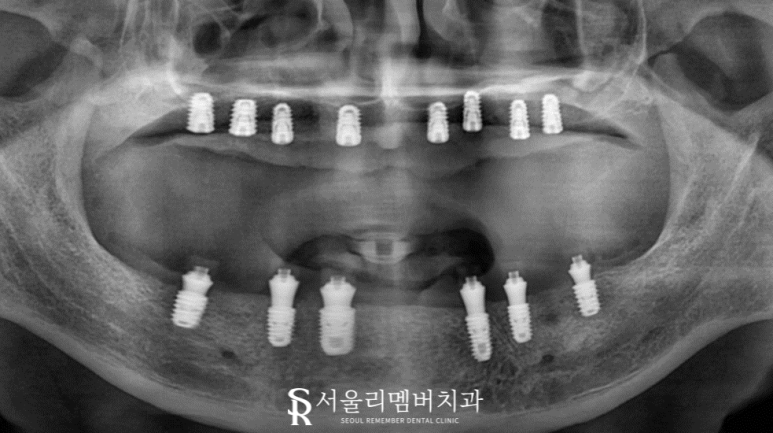

구강 내에 단 4개의 치아만이 남아있었고 오랜 의치 착용으로 잇몸뼈가 상당 부분 소실되어 있었습니다.

이 환자께 딱 알맞은 방법은 '전체 식립'이라는 생각이 들었습니다.

따라서 정확하고 안전한 진행 방식을 택하여 기간은 좀 걸리지만 건강에 영향을 끼치지 않도록 순차적인 식립을 도와드렸습니다.

위, 아래 전체 식립이기 때문에 무엇보다 환자의 협조가 중요했는데요.

구강 상태가 별로 좋지 않았으며 연령도 높은 탓에 골융합이 잘 이뤄질 수 있을까 걱정이 되었는데요.

다행히 단단하게 잘 심어져 있는 모습이네요.